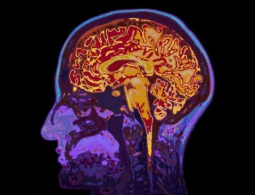

Возможность изменения воспоминаний стала еще ближе

Нейробиологи недавно обнаружили, что при формировании разных типов памяти хоть используются одни и те же нейроны, но при этом в них происходят совершенно разные процессы. Данное открытие может привести к разработке новых и более эффективных методов лечения негативных психологических состояний вроде...

Насколько оправдана шумиха на тему улучшения мозга?

Несмотря на смелые прогнозы от нескольких технокомпаний касательно будущего нейронных интерфейсов, наука расширения мозга все еще находится в зачаточном состоянии. Что же думают ученые про всю эту шумиху, которая доносится из Кремниевой долины? Михаил Лебедев, нейробиолог, работающий над нейрокомпью...